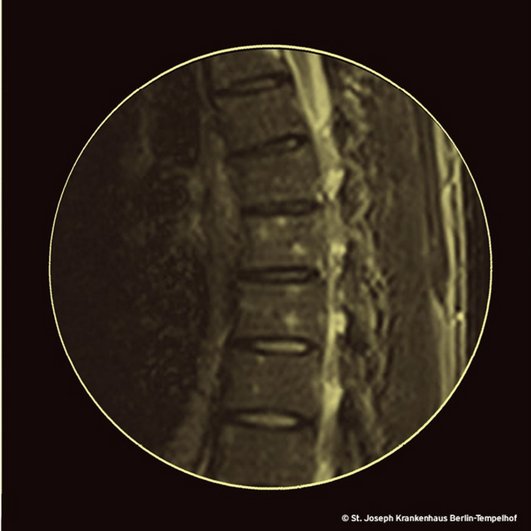

Anders als während der späten Lues (wir erinnern an die Säbelscheidentibia) ist in den frühen Stadien der Erkrankung die syphilitische Osteitis mit 15/10.000 Fällen eine Rarität [2]. Seit den 1980er Jahren tauchen allerdings immer wieder Fallbeschreibungen von Osteitiden bei Patientinnen und Patienten mit Lues II und HIV-Infektion auf [3-8]. Der hier beschriebene Fall mit seinen Herden in den Wirbelkörpern (unser Bild) ist eines der Beispiele.